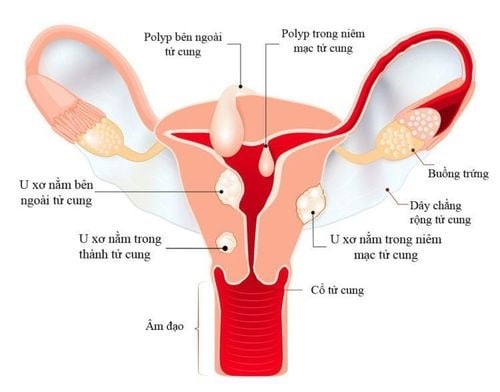

Cùng với kích thước và số lượng khối u, thì phân loại khối u cũng là điều có thể ảnh hưởng đến tiên lượng điều trị. Dựa vào vị trí của khối u có thể chia ra 3 loại u xơ chính bao gồm:

- U xơ dưới thanh mạc: Đây là loại khối u thường gặp nhất trong u xơ tử cung, khối u phát triển từ cơ tử cung hướng ra phía ngoài tử cung, tạo khối rõ ràng, có trường hợp khối u có thể có cuống gây xoắn và hoại tử u.

- U xơ trong cơ tử cung: Đây là khối u nằm hoàn toàn trong cơ tử cung, thường có nhiều khối làm cho tử cung to lên.

- U xơ dưới niêm mạc: Đây là loại u xơ ít gặp nhất, khối u phát triển từ cơ tử cung nhưng hướng và về phía lòng tử cung, đội lớp niêm mạc lên, có trường hợp khối u phát triển to ra và chiếm hết toàn bộ tử cung. Một số trường hợp u có cuống có thể thò ra ngoài dẫn tới nhiễm trùng.